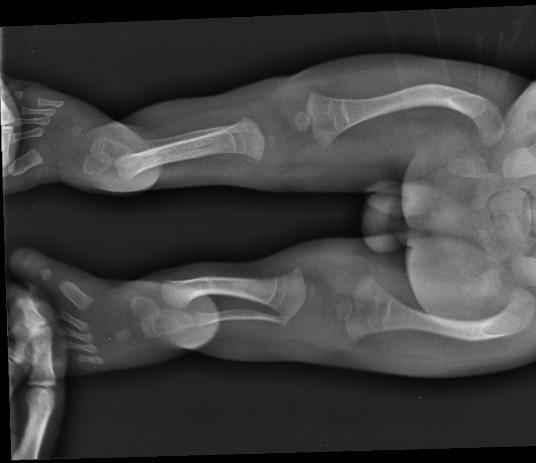

Adaś urodził się siódmego października i mimo czarnych wizji lekarzy przeżył więcej niż kilka krótkich chwil na tej ziemi. Pomimo, iż lekarze zaszufladkowali go i przykleili mu „łatkę” wrodzonej łamliwość my uparcie udowadnialiśmy im, że się mylą. I choć kazali go nie przytulać, nosić na drewnianej deseczce i najlepiej w ogóle nie rehabilitować my sami działając po omacku i kierując się własną intuicją pokonywaliśmy strach przed chorobą i z dnia na dzień, z tygodnia na tydzień byliśmy coraz odważniejsi w jego pielęgnacji uświadamiając sobie, że Adaś nie jest krucha istotką, ale silnym i walecznym młodym człowiekiem, na którego wydano niesprawiedliwy wyrok. Nasze przekonanie potwierdziły badania genetyczne, które wykluczyły wrodzoną łamliwość kości. Z czasem szukając najlepszych specjalistów z zakresu ortopedii trafiliśmy na doktora Paley, który potrafił w prawidłowy sposób zdiagnozować problem Adasia. Jego nóżki nie były nigdy złamane a jedynie wykrzywione. Obraz USG w ciąży, jak również badania RTG sprawiały mylne wrażenie kości po złamaniu.

Adaś po raz kolejny udowodnił jakim jest wojownikiem, zaczął samodzielnie chodzić. Jednak jego nóżki są w wielu miejscach bardzo powykrzywiane. Adaś potrzebuje serii operacji, które umożliwią mu prawidłowe chodzenie, uniknięcie zwichnięcia stawów biodrowych oraz poprawią komfort życia. Jego wada jest ekstremalnie rzadka a seria rekonstrukcji, których potrzebuje jest bardzo rozległa (m.in. prostowanie kości udowych, kości podudzia, rekonstrukcja stóp, korekcja bioder i wiele innych zabiegów na tzw. tkankach miękkich). Po wielu poszukiwaniach los po raz kolejny postawił na naszej drodze doktora Paleya, który ma swoją klinikę na Florydzie. Doktor podjął się leczenia Adasia, co więcej, zminimalizowania ilości operacji i tym samym zmniejszenia dziecku ilości bólu i cierpienia. Co więcej, w naszym przypadku zgodził się na wykonanie operacji w Polsce. Jest to dla nas niezwykła szansa aby zapewnić synowi prawidłowy rozwój i w miarę normalne funkcjonowanie wśród rówieśników.